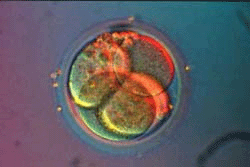

Вторые - начало третьих суток после зачатия. Бластомеров уже восемь. При искусственном оплодотворении (ребенок "из пробирки") в матку женщины подсаживают именно такой зародыш.

Это бластоциста. Похожа на тутовую ягоду?